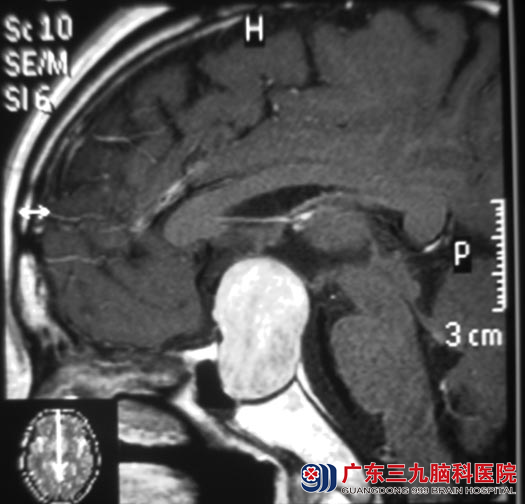

广东三九脑科医院垂体瘤诊疗中心 鲁明主任给陈先生查体发现:左侧视力为眼前指数约10cm,颞侧视野偏盲,右眼视4.8;头颅MR检查见蝶鞍内与鞍上示一较大的略呈“葫芦”样肿块影,大小约34.0mm×25.9mm×29.1mm,内分泌检查提示FT445.09pmol/L,T0.268 ug/L,T4,266nmol/L,T35.077nmol/L,经内分泌专家会诊暂不考虑甲亢。

▲手术前